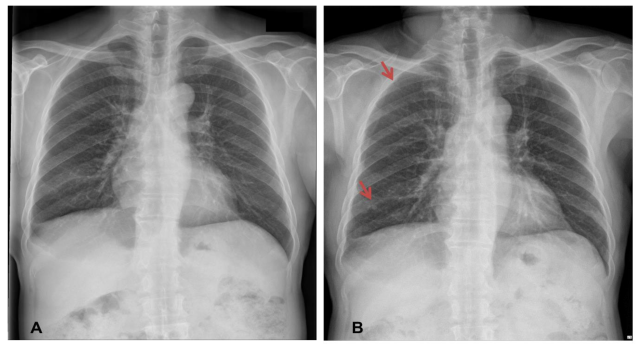

肺部纤维化,源:Nephron

一旦被人体摄入,这些“原纤维”就会堆积在人的肺组织或体内的膜衬里,并逐渐导致细胞死亡,随着时间推移,这个过程就会引发癌变。

石棉引发的癌症包括间皮瘤,肺癌,喉癌,卵巢癌等等,由于癌症的引发需要很长时间——有时候可能需要20年之久,所以许多人可能并没有把癌症和石棉相关联。